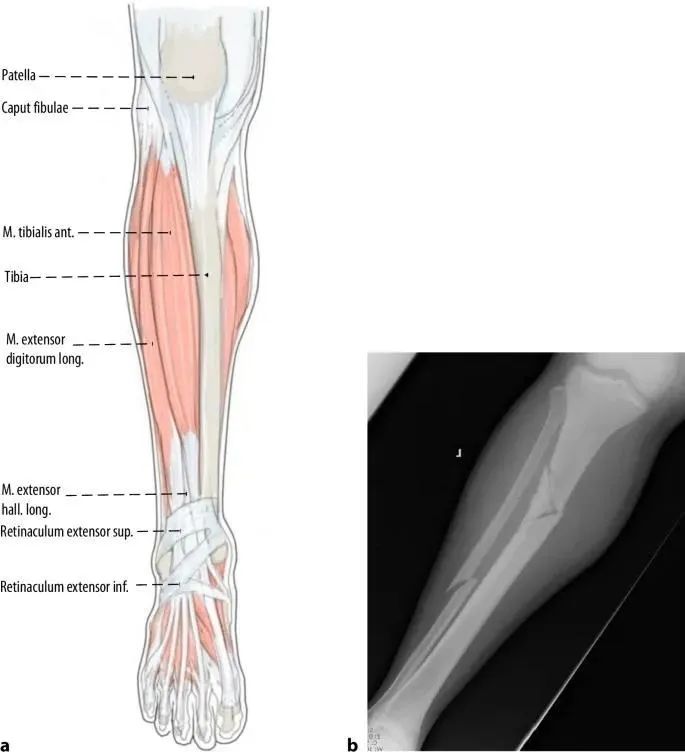

La principale cause de désalignement dans les fractures tibiales proximales est la déformation causée par la traction du tendon du quadriceps lors de la flexion du genou et le conflit mécanique entre la pointe de l'ongle et le cortex tibial postérieur lors de l'insertion de l'implant.La rotule empêche également l'entrée axiale du clou dans le plan sagittal (Fig. 1a, b).Par conséquent, une autre méthode courante d'accès au point consiste à effectuer une incision parapatellaire médiale, qui conduit à une légère insertion médiale à latérale du clou (Figs. 1c et 2).Lorsque le clou pénètre dans le canal intramédullaire en aval de la fracture, la partie proximale s'incline en valgus (Figure 2).Enfin, la tension de repos des muscles de la loge antérieure contribue légèrement au valgus (Figure 3).

Figure 1 a,b En utilisant l'approche infrapatellaire conventionnelle, la rotule empêche l'entrée axiale du clou, ce qui entraîne la déformation courante de l'alignement sagittal apical antérieur et de l'alignement coronal en valgus.c Utilisation de l'approche parapatellaire pour l'alignement du clou centromédullaire.

Figure 2 L'approche du point d'entrée par une incision parapatellaire médiale conduit à une insertion légèrement médiale à latérale du clou.Lorsque le clou pénètre dans le canal médullaire en aval de la fracture (a), la partie proximale s'incline en valgus (b)